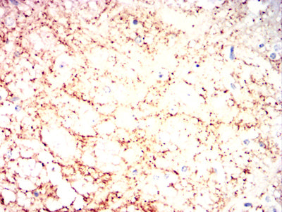

VAMP2 Mouse Monoclonal antibody[5A2C7]

IHC    1/200 - 1/1000